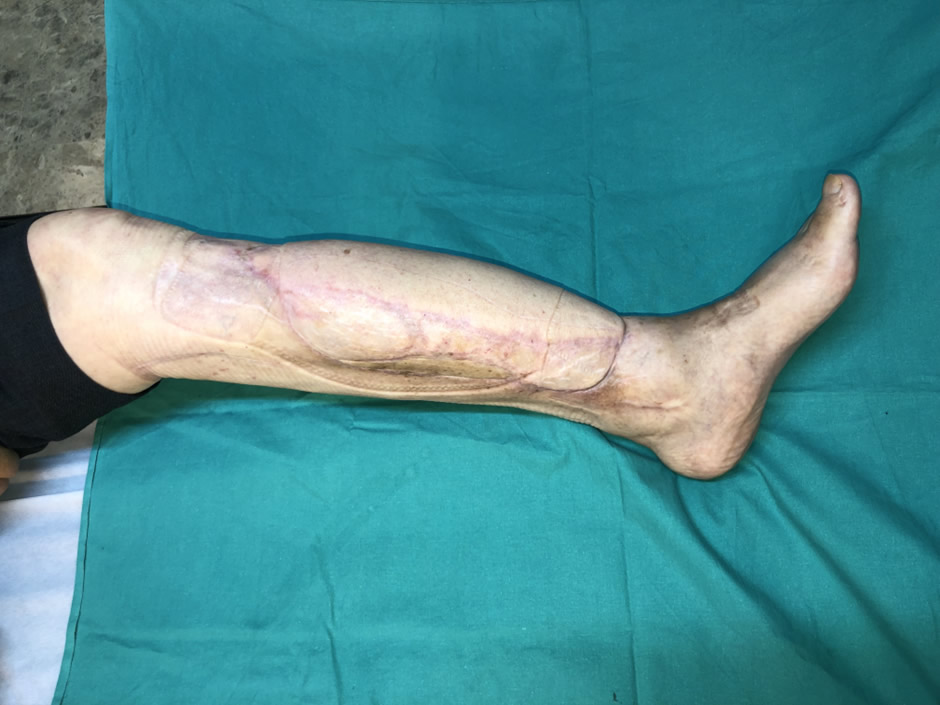

03. Resultado

Tras 30 años de evolución la infección se curó y el paciente puede caminar con esqueleto estable, indoloro y alineado. Un resultado que demuestra que ninguna osteomielitis crónica es incurable con el tratamiento quirúrgico adecuado.

- Curación de la osteomielitis crónica de 30 años de evolución

- Reconstrucción de la tibia — esqueleto en continuidad

- Deambulación autónoma recuperada